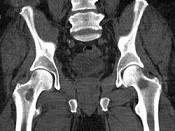

问题 男,46岁,双髋关节疼痛,反复感染,贫血,实验室检查血钙升高,本周蛋白尿(+),结合图像,最可能的诊断是()

选项 A.骨髓瘤 B.骨质疏松 C.骨转移瘤 D.骨囊肿 E.动脉瘤样骨囊肿

答案 A